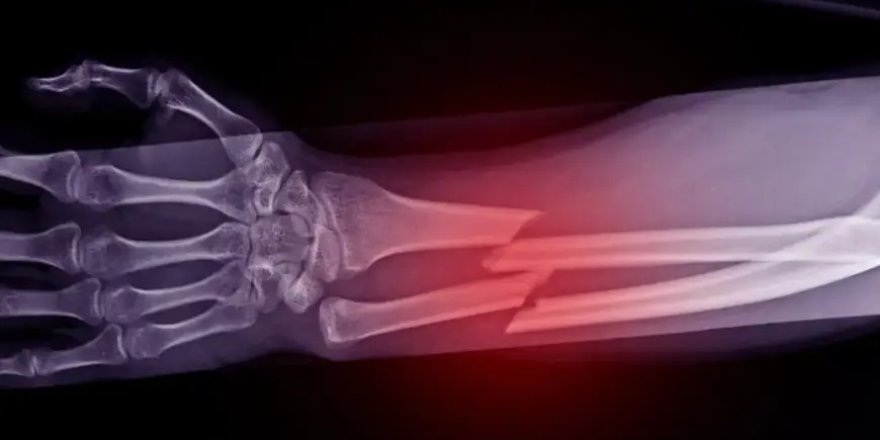

Çinli bilim insanları, kemik kırıklarının tedavisinde devrim yaratabilecek yeni bir biyoyapıştırıcı geliştirdi. “Bone-02” adı verilen bu özel formül, deniz canlılarının doğadaki yapışma mekanizmalarından esinlenerek hazırlandı ve yalnızca üç dakika içinde kemik kırıklarını kalıcı şekilde onarma potansiyeline sahip.

Kanlı ve nemli ortamlarda dahi güçlü tutunma sağlayan yapıştırıcı, vücut tarafından emilebilmesi sayesinde ikinci bir cerrahi müdahaleye gerek bırakmadan kemik iyileşmesini destekliyor. Çin basınına göre “Bone-02” bugüne kadar 150’den fazla hastada başarıyla denendi.

Teknik testlerde yapıştırıcının bağlanma kuvvetinin 180 kilogramın üzerinde, kayma dayanımının 0,5 megapascal, basma dayanımının ise yaklaşık 10 megapascal olduğu bildirildi. Bu değerler, yapıştırıcının yalnızca kısa süreli bir sabitleme değil, günlük yaşamda kemiğin maruz kalacağı kuvvetleri taşıyabilecek kalıcı bir onarım sağladığını gösteriyor.